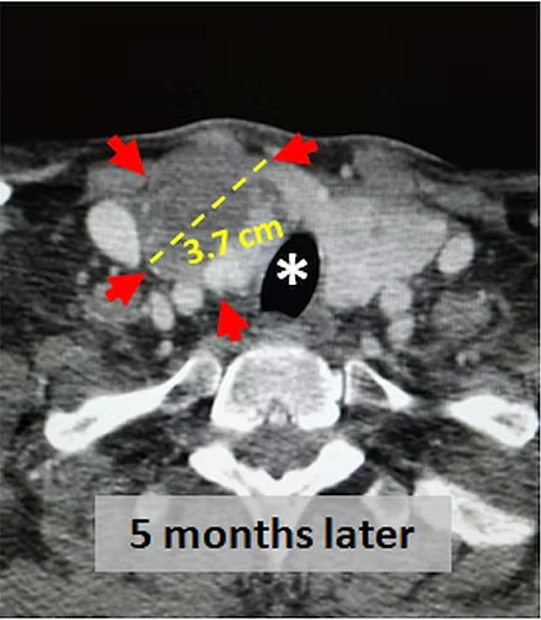

The thyroid gland has generally four feeding arteries and they also supply four parathyroid glands. This, to prevent hypothyroidism and hypoparathyroidism, 2 or 3 out of 4 feeling vessels are embolized and at least one vessel is left intact. If both thyroid lobes require treatment, embolization can be done first to one lobe, and some months later, to the other lobe. After the embolisation, the thyroid nodules become dead and shrink rapidly. If there is hyperthyroidism as in Graves disease or toxic nodule(s), the TSH, T3 and T4 labels either improve or return to normal. After the embolisation, patients may experience some neck pain and temporary hyperthyroidism for some weeks.

In thyroid diseases, the most common treatments are surgery RAI and percutaneous ablation. Embolisation is performed in patients who are not suitable for or do not desire these treatments. For example, in large plunging goiters, surgery is generally difficult since anesthesia is challenging and chest must also be opened besides the neck. In such cases, embolisation may be done easily and effectively. After the procedure, the goiter may become smaller and compressive symptoms such as shortness of breath, swallowing difficulty hoarseness may improve. In Graves disease similarly, embolisation results in lowering or normalization of thyroid hormones in more than 70% of the cases. If the hyperthyroidism is caused by nodule(s) in a MNG patient, embolization can not only make the nodule(s) smaller also correct the hyperthyroidism. Similarly, in patients with a single large (more than 6 cm) nodule, embolisation of the nadule is very effective in reducing its size. In such large nodules, percutaneous ablation is generally not very effective.